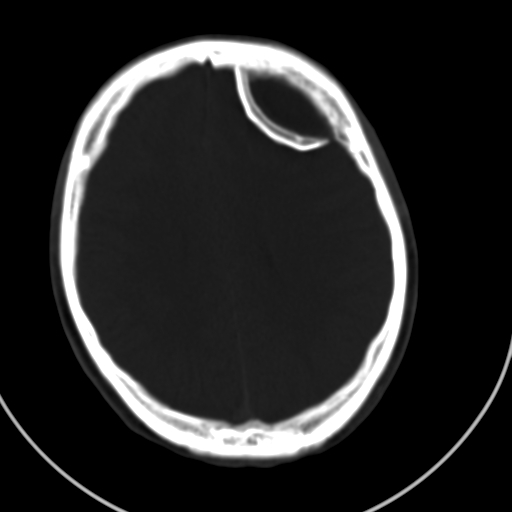

标题: CT21939:男20岁,外伤一年后,现头疼. [打印本页]

标题: CT21939:男20岁,外伤一年后,现头疼.

凹陷的很像颅骨内板。

如果是骨折,外板正常内板这么明显凹陷,请问这样的骨折是怎样形成的?形成的机理是什么?有没有可能形成?

左侧额部硬膜外血肿机化、骨化。

左侧额部硬膜外血肿机化、骨化